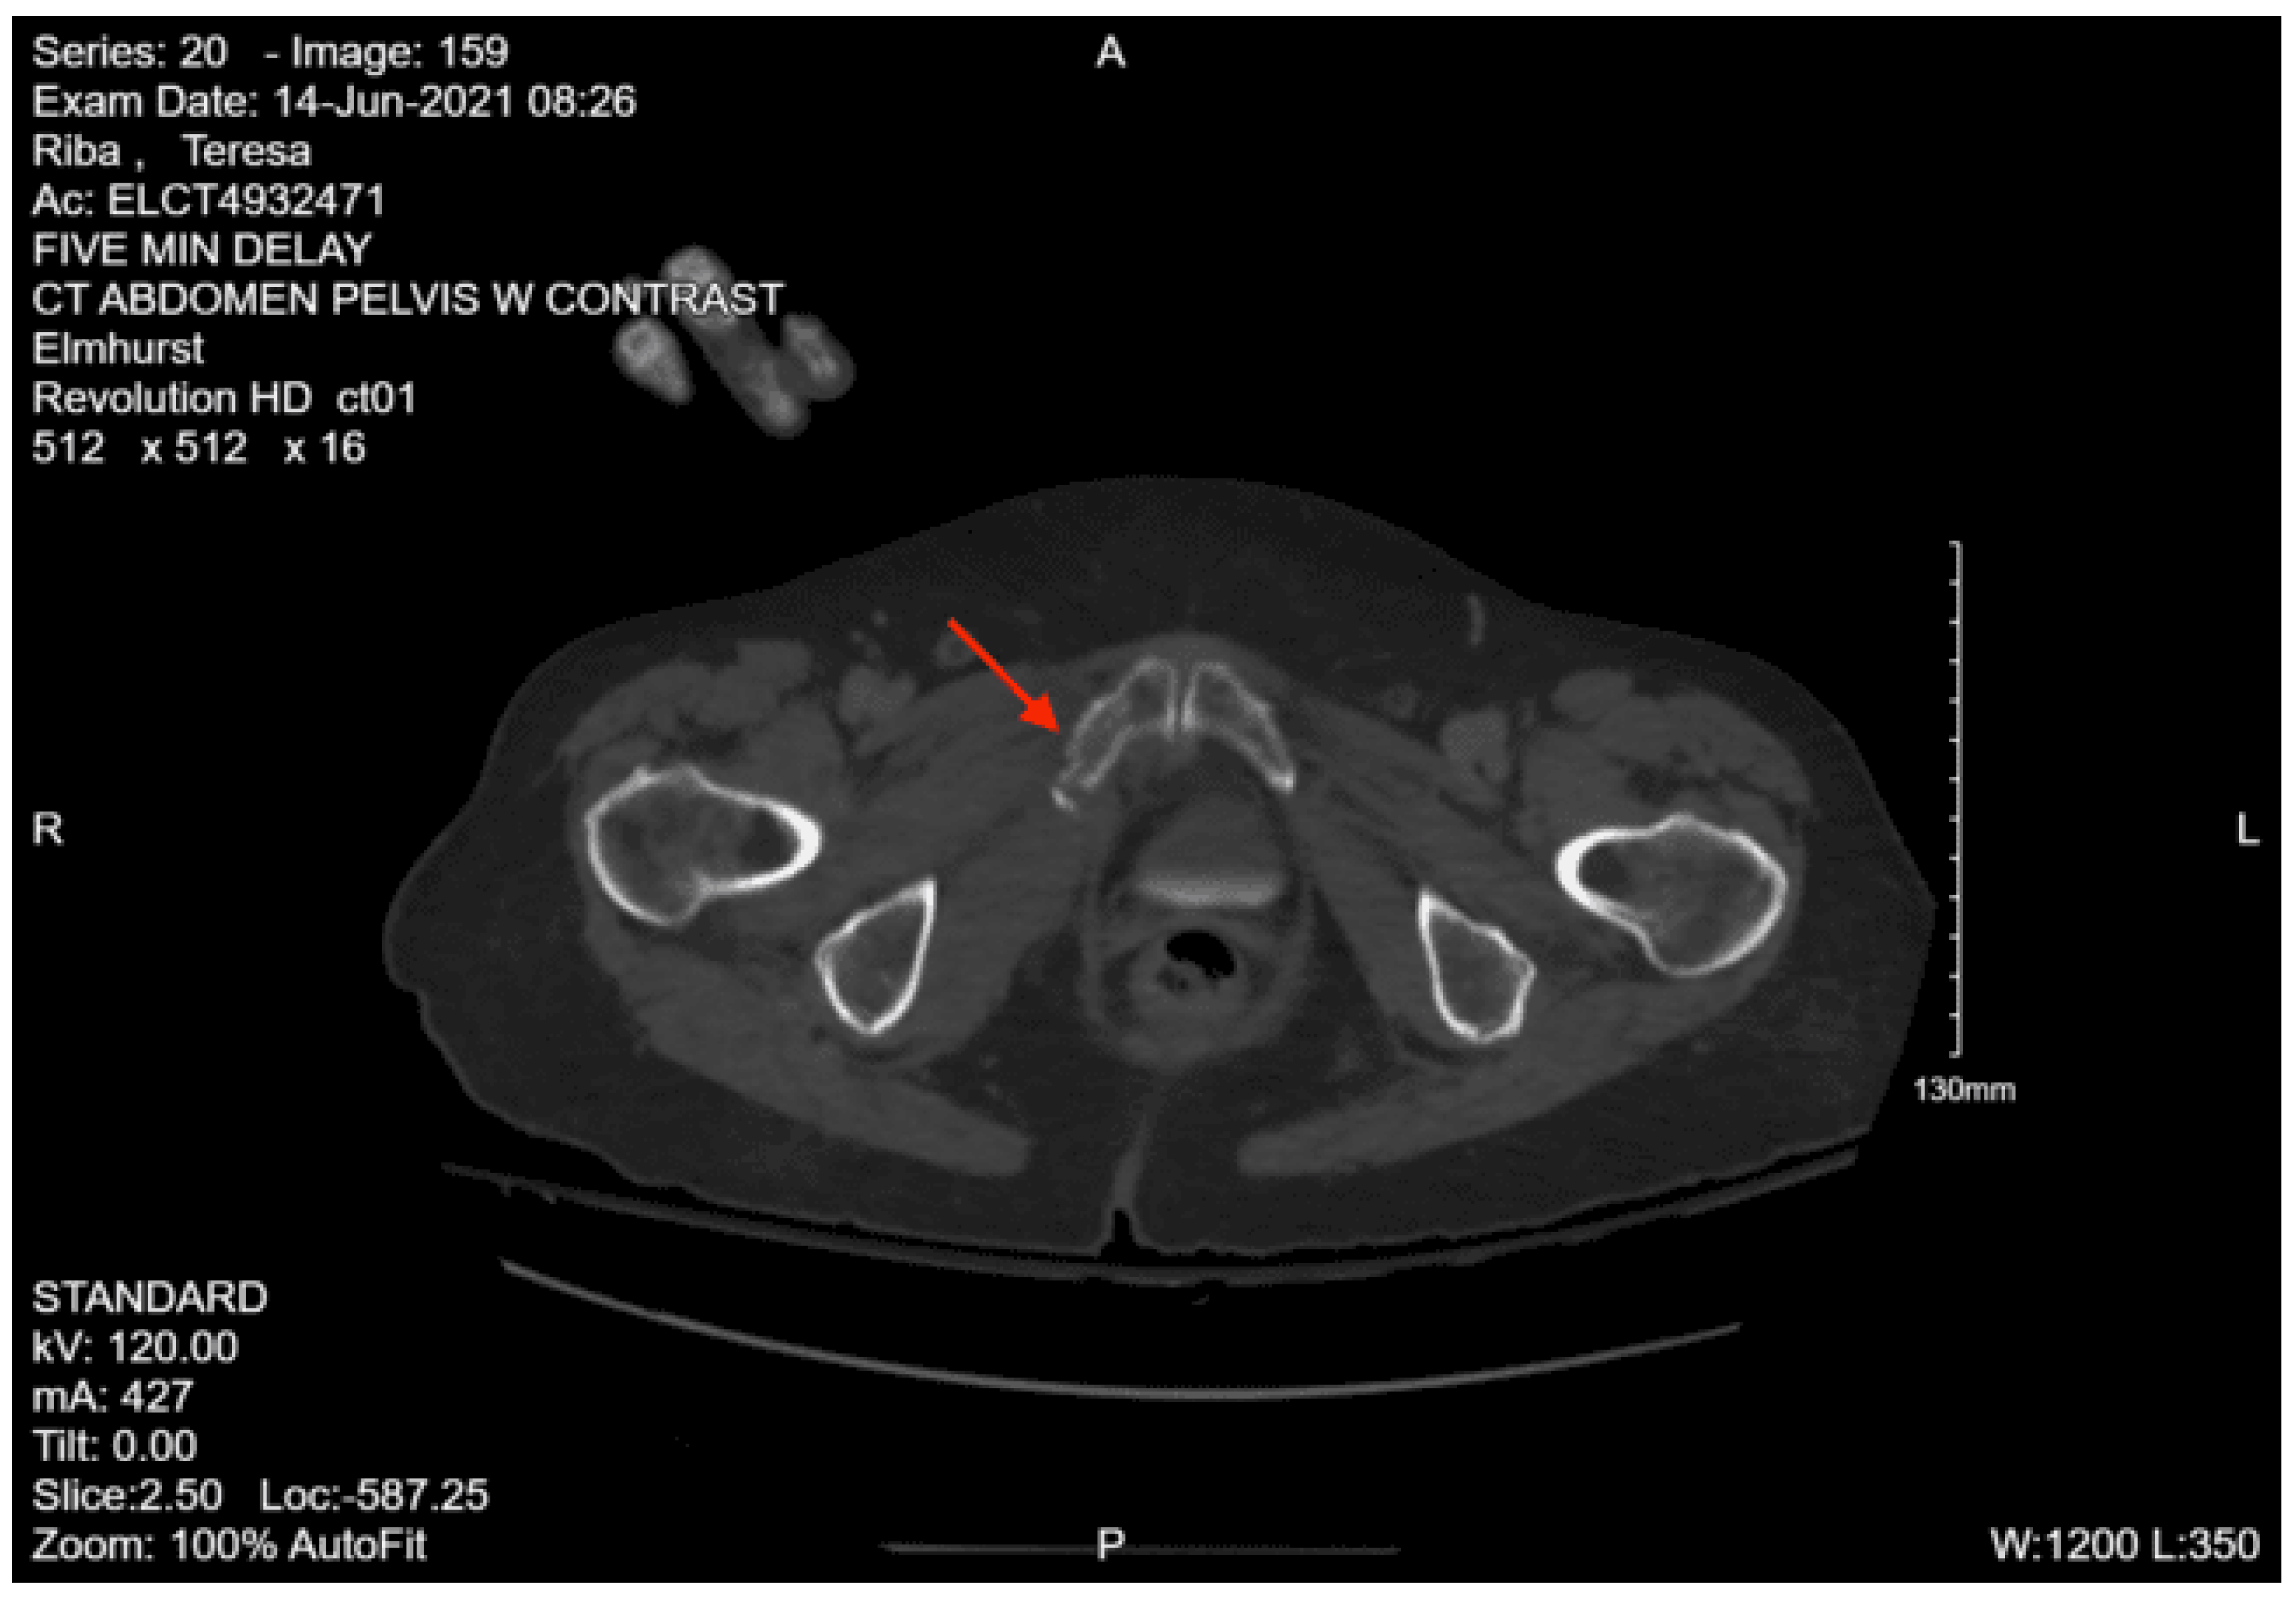

CT abdomen and pelvis with contrast: No acute visceral traumatic abnormality. There is evidence of an acute impacted fracture involving the left superior and inferior pubic rami. The right superior and inferior pubic rami are intact. The sacrum and coccyx appear unremarkable.

During her hospital course, the patient was also found to have a right lateral tibial plateau fracture and bilateral sacral ala fractures; orthopedic surgery recommended non-weight bearing for the RLE, and neurosurgery recommended bed rest. She required multiple blood transfusions due to repeated drops in hemoglobin/hematocrit but remained hemodynamically stable. Given her continued intubation status, tracheostomy was performed on hospital day 8. Continued monitoring via CT head with and without contrast continued to show evolving strokes and persistent severe vasospasm. On hospital day 13, the patient was seen by physical medicine and rehabilitation, who recommended physical and occupational therapy and TBI unit vs sub-acute rehab for discharge when the patient was medically stable. The patient’s mental status gradually started to improve, and she was transferred to the surgical stepdown unit on hospital day 15. On hospital day 19, PEG was placed by interventional radiology. The patient continued to slowly improve, and tracheostomy decannulation was performed on hospital day 36; then she was discharged to TBI rehab 3 days later.